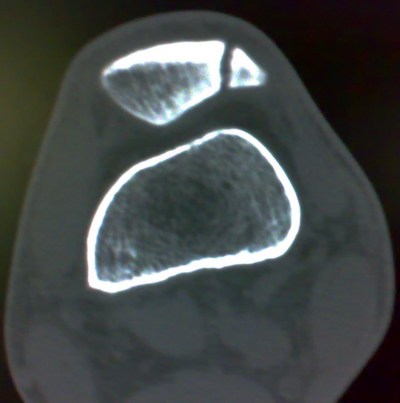

标题: X7705:上传CT结果:二分髌骨 [打印本页]

标题: X7705:上传CT结果:二分髌骨

上传ct结果:二分髌骨

符合二分髌骨表现。